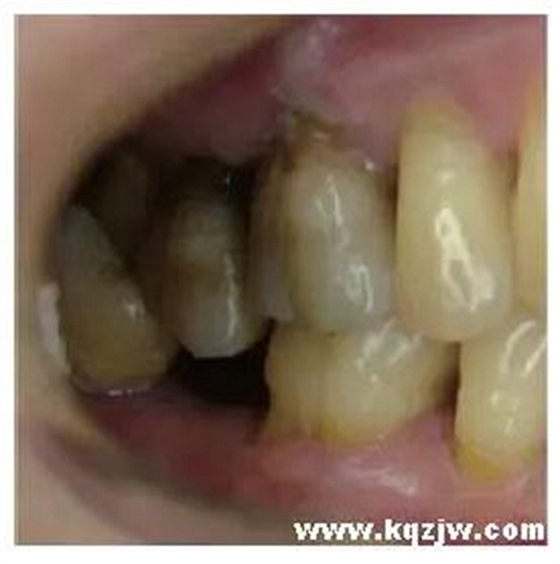

凸凹不吻合型接觸

凸凹吻合的咬合接觸一方面與牙的(牙合)面形態(tài)有關(guān),更主要的是與牙的位置有關(guān)。如果牙的位置不正常,例如牙易位、轉(zhuǎn)位、高位、低位等,也將影響上下牙的凸凹接觸。常見的異常表現(xiàn)是后牙缺失久未修復(fù)形成鄰牙傾斜、對(duì)頜牙伸長后,傾斜的鄰牙與伸長的對(duì)頜牙之間的非軸向咬合接觸(圖6),以及第三磨牙因萌出位置不佳而形成的各種異常咬合接觸(圖7、8)。這些咬合接觸既對(duì)咬合時(shí)下頜的位置有嚴(yán)格限定,又不能實(shí)現(xiàn)穩(wěn)定的凸凹接觸關(guān)系,也不能引導(dǎo)協(xié)調(diào)的下頜運(yùn)動(dòng),是對(duì)咀嚼功能危害較大的一種咬合接觸關(guān)系。

圖6 下頜第二磨牙(47)缺失導(dǎo)致上頜第二磨牙(17)伸長和下頜第三磨牙(48)向近中傾斜,48和17形成非軸向咬合接觸